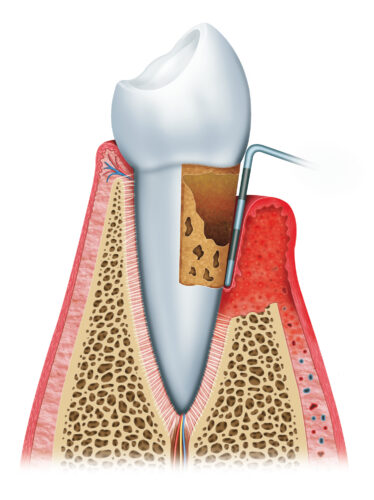

三、中度牙周炎

隨著細菌進一步破壞造成齒槽骨流失,牙周囊袋也越來越深,臨床上牙齦會持續發炎,甚至產生膿包。牙齒也因牙齦萎縮而使牙根暴露,容易對冷熱敏感,牙齒外觀看起來變長了,牙根之間出現縫隙,患者可能會感到咀嚼時無力,且牙齒咬合方式改變。